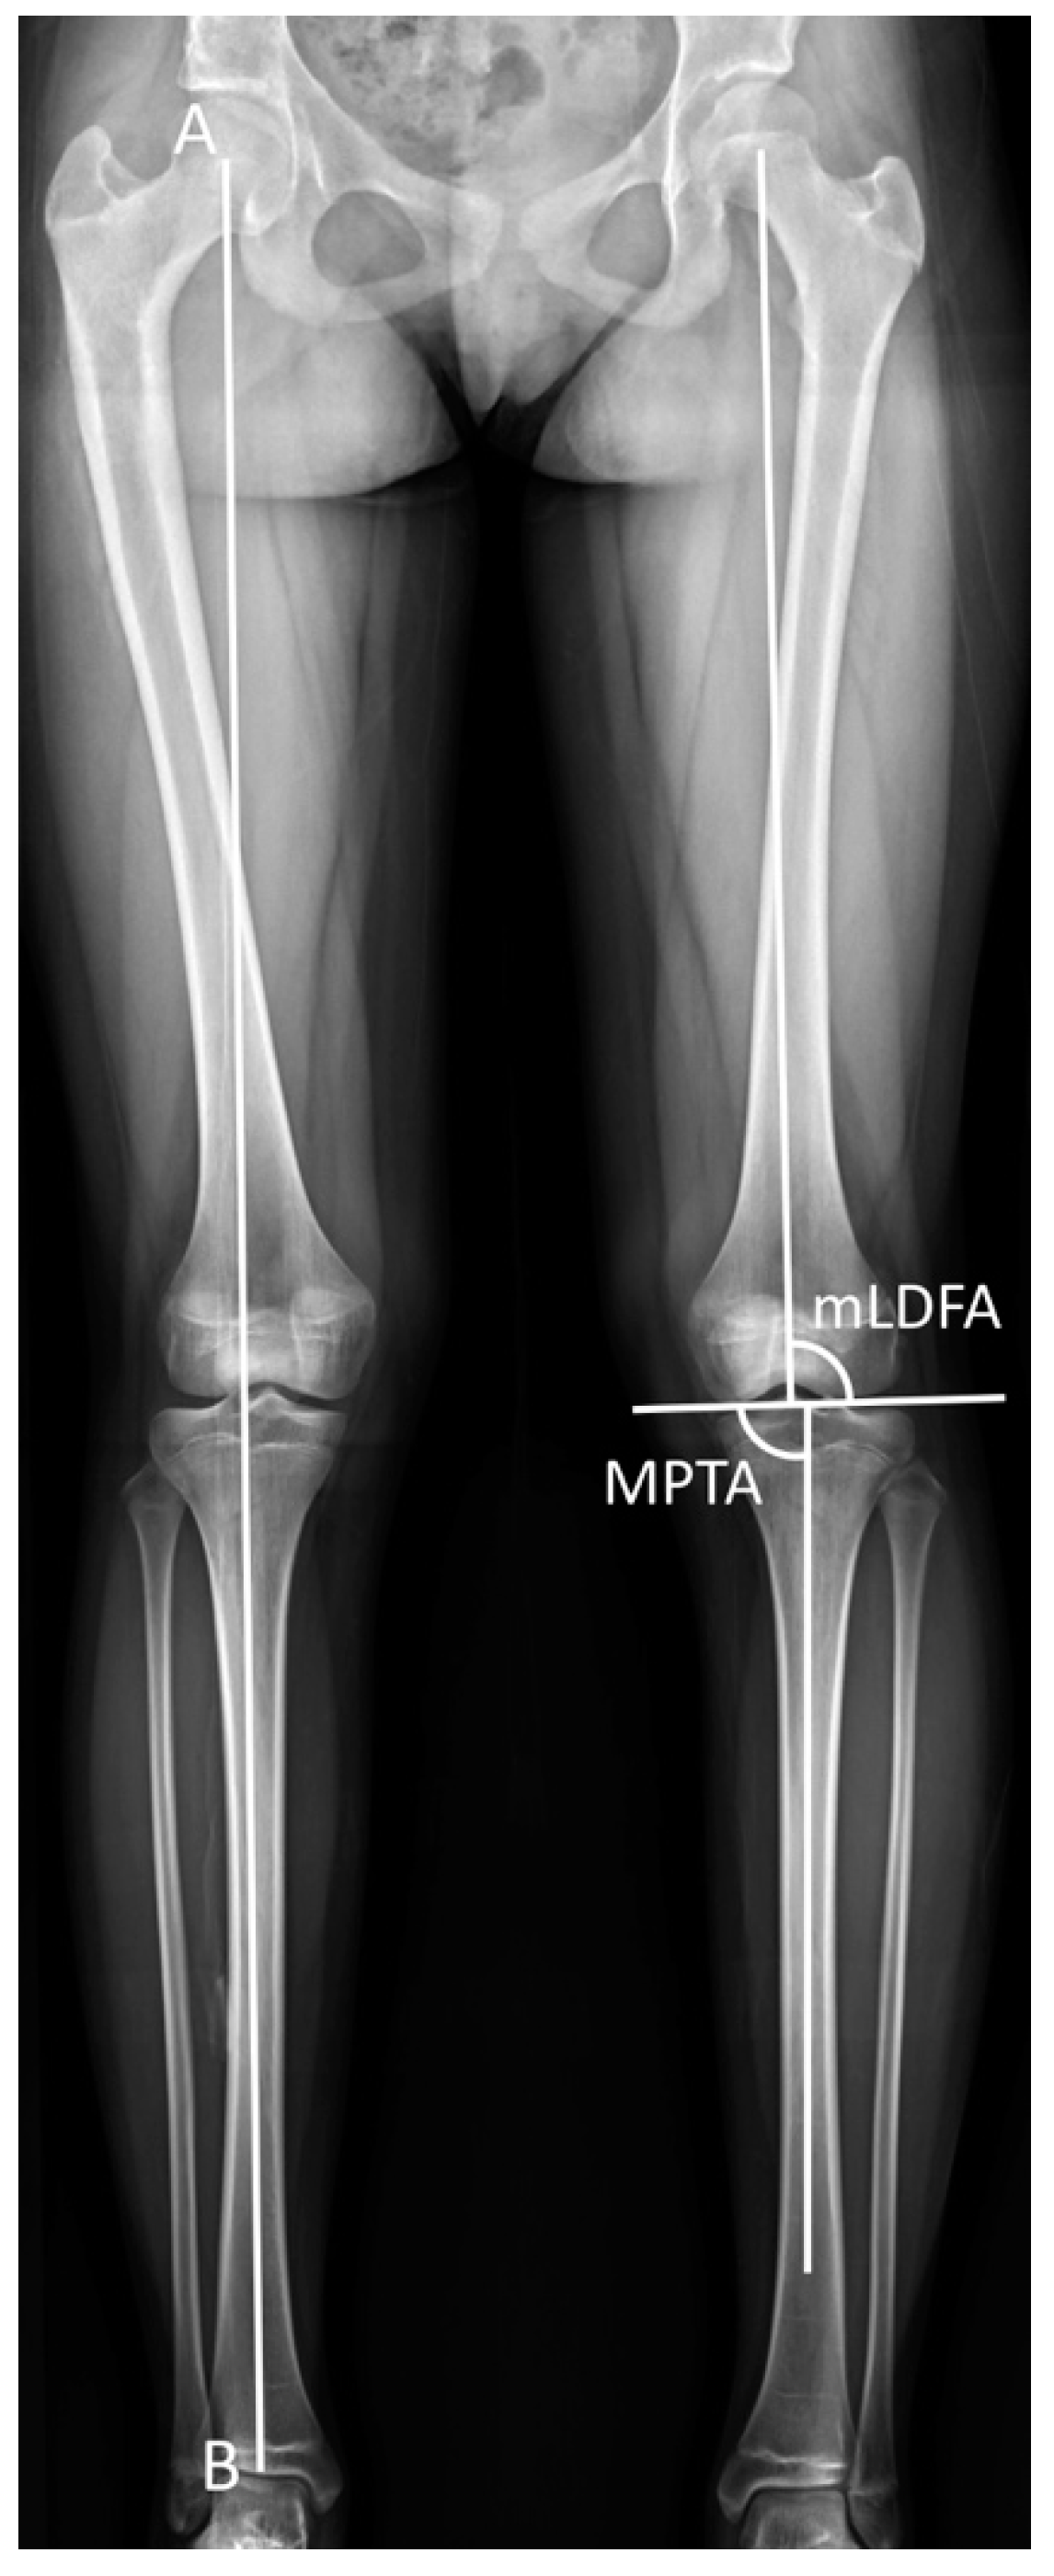

The scanogram was taken in a standing position with both knees fully extended and patellae facing forward. The tibia radiographs were obtained at each clinic visit. The radiographic parameters included leg-length discrepancy, tibial length, length gained, mechanical lateral distal femoral angle (mLDFA), medial proximal tibial angle (MPTA), and mechanical axis deviation (MAD) (Figure 1). The tibial length was measured from the tibial spine to the center of the tibial plafond. The length gained was defined as the increase in length of the operated limb. The mLDFA was defined as the lateral angle between the joint surface of the femoral condyle and the femoral mechanical axis, and the MPTA was defined as the medial angle between the articular axis of the proximal tibia and the tibial anatomical axis [18]. The distance from the center of the knee to the mechanical axis of the lower leg was labeled as the MAD [18]. The MAD was denoted as valgus or varus malalignment when the mechanical axis showed a lateral or medial deviation [18].

Figure 1. Radiological measurements. The superolateral angle between the mechanical axis of the femur and the joint surface of the femoral condyle was defined as the mechanical lateral distal femoral angle (mLDFA). The inferomedial angle between the anatomical axis of the tibia and the articular axis of the proximal tibia was labeled as the medial proximal tibial angle (MPTA). The mechanical axis deviation (MAD) was designated as the distance from the center of the knee to the mechanical axis of the lower leg. Mechanical axis = AB.